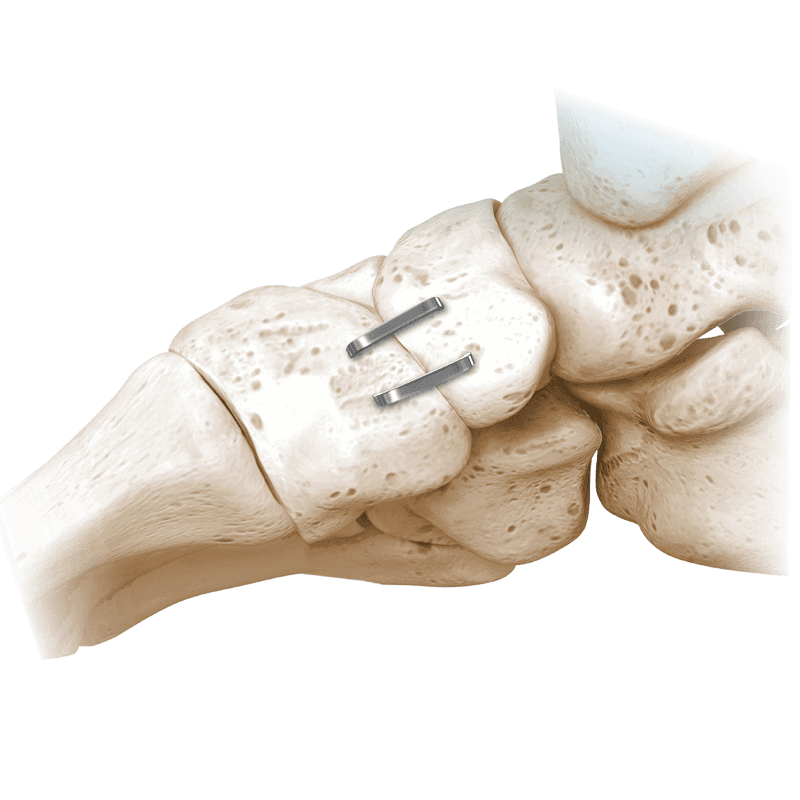

NeoSpan® SE Compression Staples

A superelastic compression-ready fixation system designed for fixation of fractures, fusions, or osteotomies